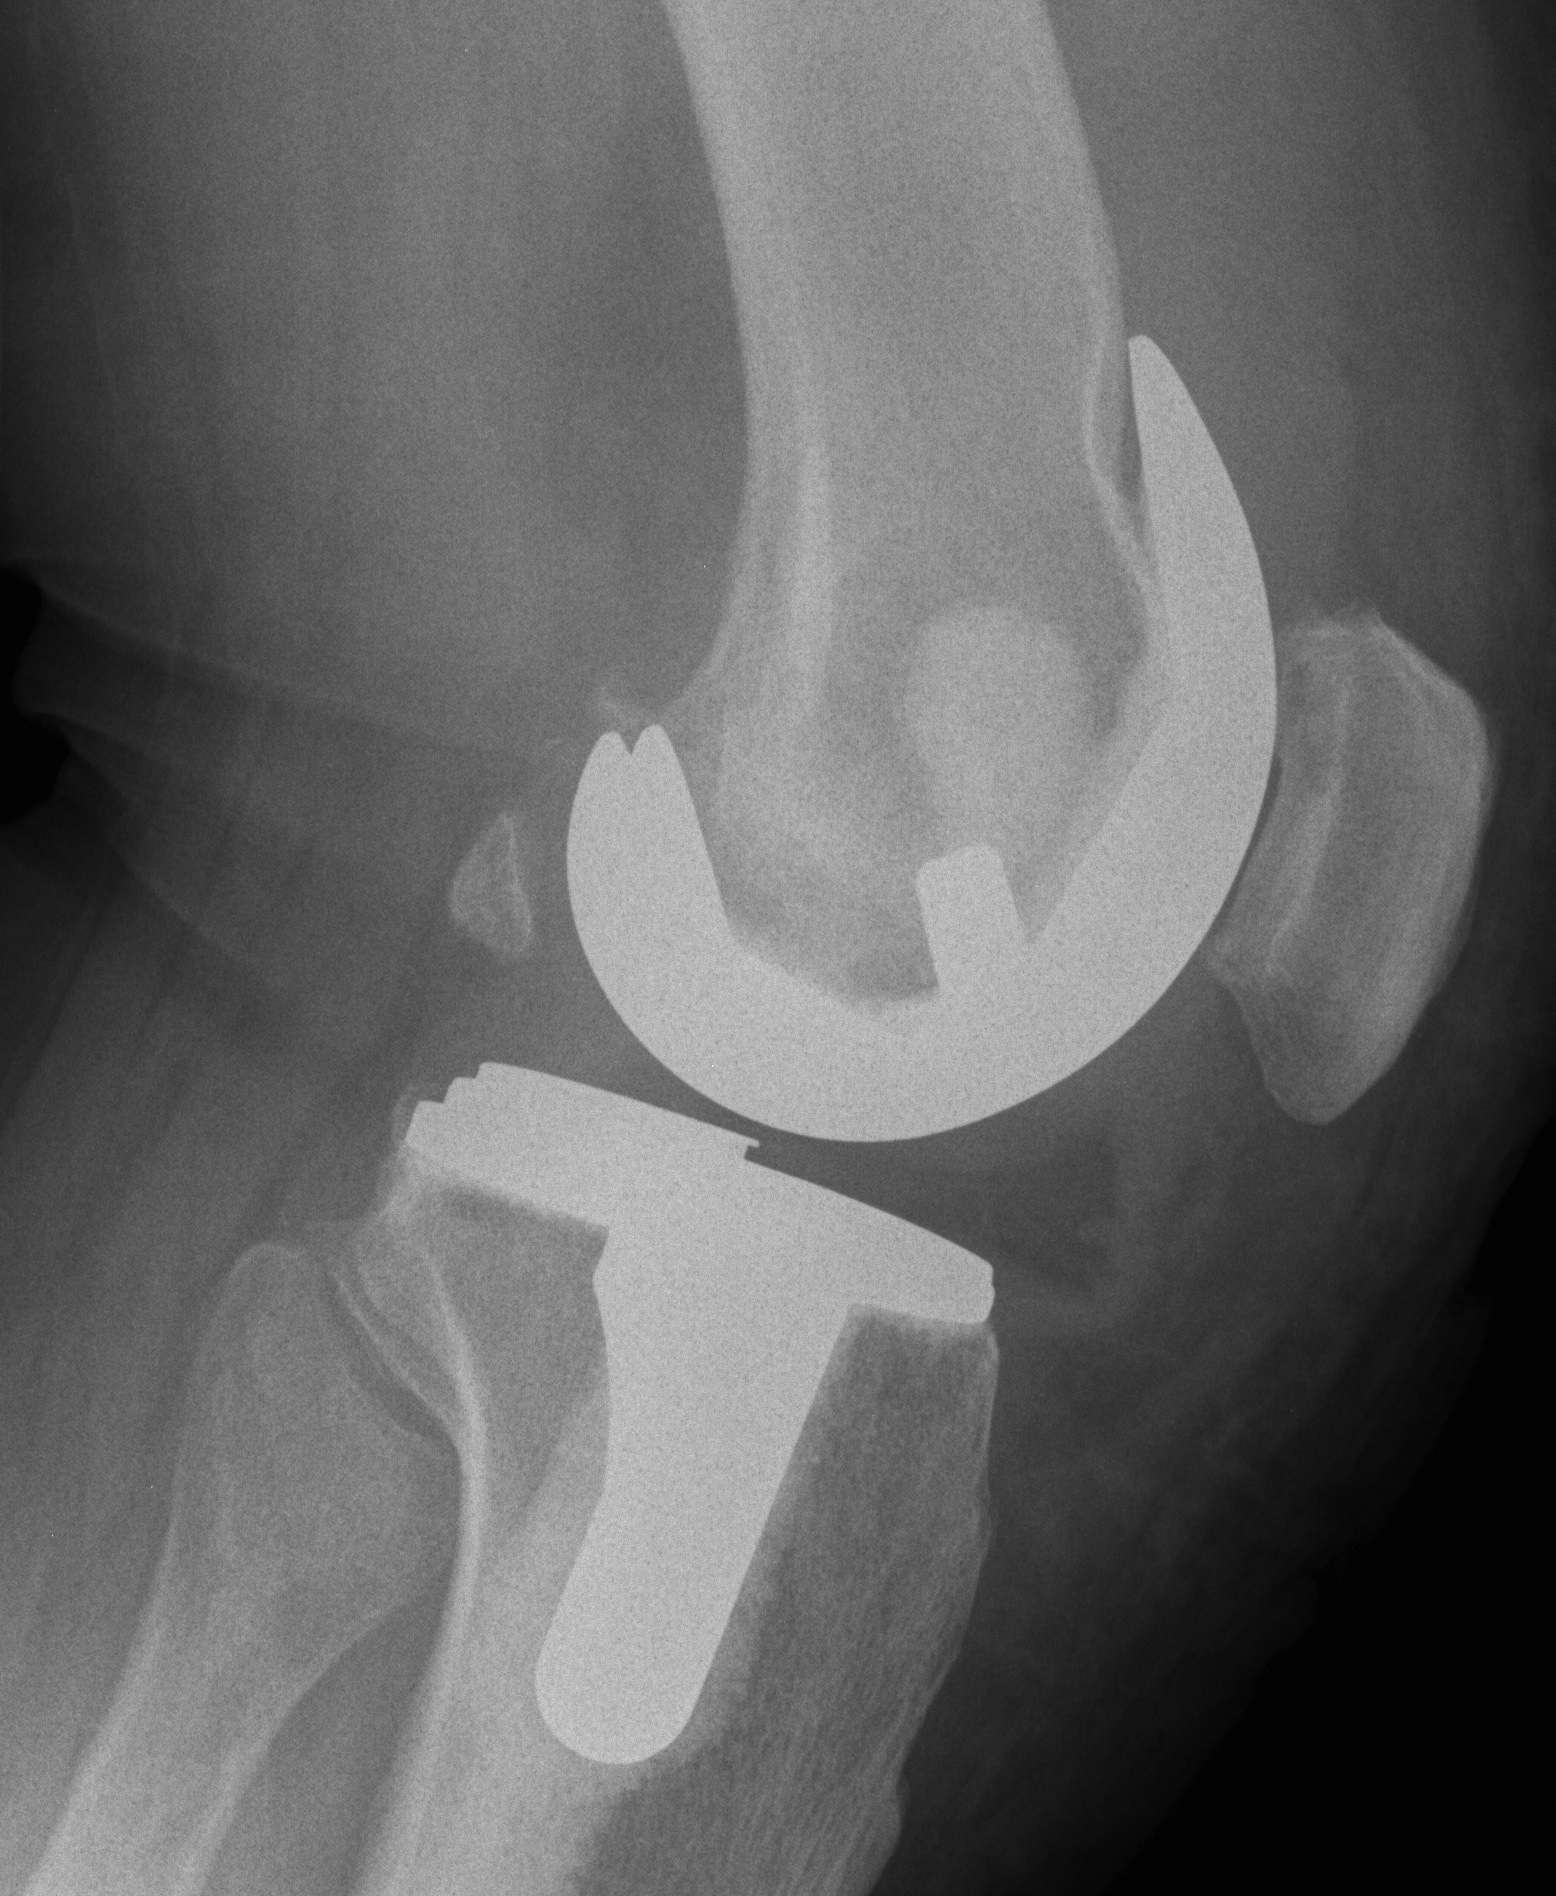

Fixation

Best technique controversial

Options

1. Cemented

2. Press-fit with porous ingrowth

3. Hybrid

Cemented

Current standard

- longest follow up

- cement "Seal" to particle migration

- easier to revise if infected

Uncemented

Initial results comparable

Risks

- very difficult to remove well fixed uncemented infected TKR

Advantage

- faster operation

Results

Baker et al JBJS Br 2007

- RCT of PFC cemented v uncemented

- 15 year follow-up

- 80% 15 year survival in cemented

- 75% 15 year survival in uncemented

Australian Joint Registry 2010

9 year survival

- cemented TKR 5.0%

- uncemented TKR 5.2%

- hybrid TKR 4.9%